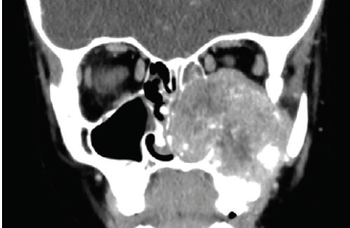

A 6-year-old boy presented to his pediatrician with clear drainage from his left eye for 1 to 2 days. He denied itchiness, pain, vision changes, nasal congestion, or history of allergies. What's the diagnosis?